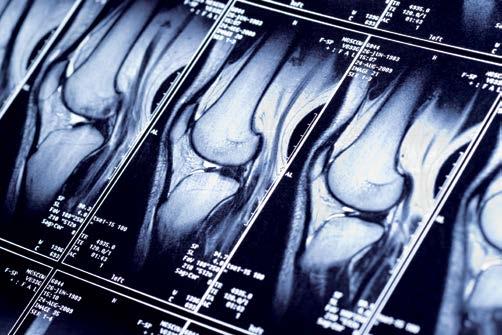

Magnetna rezonanca u dijagnostici mišićno-koštanog sistema

Precizne i detaljne slike sportskih povreda

Zahvaljujući tome što izvanredno prikazuje kontraste između različitih tkiva, magnetna rezonanca je bez premca ne samo u proceni patoloških promena u mozgu i kičmenoj moždini, već i u mišićima i drugim strukturama koštano-zglobnog sistema kao što su: meniskusi, tetive i ligamenti. Za razliku od rentgena i skenera (CT - kompjuterizovane tomografije), magnetna rezonanca omogućava vrlo detaljno i precizno dijagnostikovanje oboljenja međupršljenske hrskavice, odnosno diskusa, kao i procenu stepena zloćudnosti i raširenosti tumora kičmenog stuba, kostiju i zglobova. Dr Akerman takođe ističe da magnetna rezonanca (MR) ne emituje štetno jonizujuće zračenje, te je sam MR pregled bezbedan za pacijente, uključujući i malu decu i trudnice (nakon prvog trimestra trudnoće). Šta više, i kontrastna sredstva, koja se u pojedinim slučajevima koriste pri MR pregledu, ne pripadaju grupi jodnih kontrasta pa je i mogućnost pojave alergijskih reakcija koje bi bile opasne po pacijenta svedena na minimum.

Zahvaljujući tome što izvanredno prikazuje meka tkiva i kosti, magnetna rezonanca je bez premca u proceni patoloških promena u kičmenoj moždini, mišićima i vezivnim tkivima koštano-zglobnog sistema. Nema superiornije metode ni u proceni oštećenja hrskavičavog tkiva zglobova, kaže dr Dejan Akerman, radiolog u BelMedic-u

Magnetna rezonanca je dominantna metoda i u dijagnostici patologije koštano-zglobnog sistema, uključujući i sportske povrede. Prema dijagnostičkom algoritmu koji se odnosi na zglobove, MR pregledu obavezno prethode klinički pregled (ortopeda, fizijatra ili reumatologa) i rentgensko snimanje, te i kod sumnje na prelom kosti radiološka dijagnostika obavezno započinje rendgenskim pregledom.

Još jednom ukazujući na to da je magnetna rezonanca suverena u utvrđivanju stanja mekih tkiva mišića i vezivnih tkiva sa visokim sadržajem kolagena, kao što su meniskus, ukršteni ligamenti i tetive, dr Akerman kaže da je metoda nezamenjiva za pregled zglobova (kolena, ramena, kuka) zato što sa najoštrijim detaljima prikazuje svaku promenu unutar zgloba. Takođe, magnetnom rezonancom se najpouzdanije detektuju i sve reumatske i nereumatske promene na malim zglobovima šaka i stopala. Kod većine pregleda zglobova, upotreba kontrastnih sredstava, bilo intraartikularno ili intravenski, danas nije potrebna. Zahvaljujući tome, ovi pregledi su dosta kraći od MR pregleda drugih regija i drugih organa, i prosečnu traju dvostruko kraće od ostalih - između 15 i 25 minuta. Govoreći o patologiji kolenog zgloba, dr Akerman kaže da je najčešće reč o traumatskim povredama kolena, posebno sada u sezoni zimskih sportova, te da osim magnetne rezonance ne postoji druga metoda koja bi preciznije pokazala oštećenja ligamenata, pre svega meniskusa. Kao i kod ostalih zglobnih i vanzglobnih oboljenja, magnetnom rezonancom se najbolje vrši trijaža pacijenata da li su za konzervativno ili za hirurško lečenje.

Kod zgloba kolena je najvažnije proceniti da li je došlo do težih oštećenja meniskusa i da li je nastupila kompletna ili nekompletna ruptura ligamenata koji daju stabilnost kolenu. Većina oštećenja ligamenata, kao i samih meniskusa, može da se zbrinjava artroskopski, minimalno invazivnom hirurškom procedurom koja ne povređuje hrskavicu i vrlo retko dovodi do traumatskog intraartikularnog krvarenja. Time se prevenira kasniji razvoj sekundarnog osteoartritisa, kao moguće posledice traumatskog delovanja otvorenih operacija. Magnetna rezonanca je, takođe, jedina dijagnostič- ka procedura koja precizno procenjuje oštećenja artikularne (zglobne) hrskavice, što je posebno važno kod mlađih osoba, naročito kod sportista. Takođe, kad se erozija zglobne hrskavice dijagnostikuje precizno i na vreme, magnetnom rezonancom, blagovremeno može da se primeni najsavremeniji oblik lečenja, takozvana osteohondralna alograftna transplantacija.